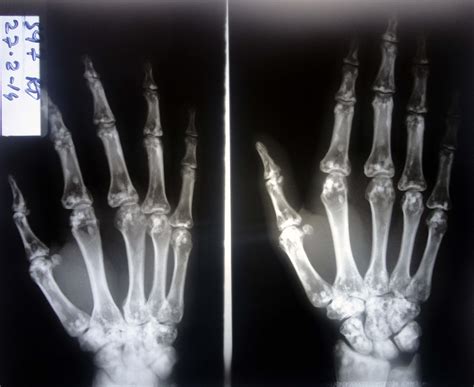

A Hand X Ray is a type of radiography that uses electromagnetic radiation to produce images of the internal structures of the hand. This process involves passing X-rays through the hand and capturing the resulting image on a detector. The varying densities of different tissues—such as bone, muscle, and fat—absorb the X-rays differently, creating a contrast that allows for detailed visualization.

• Fractures and Dislocations: X-rays are the primary method for diagnosing broken bones and dislocated joints in the hand.

• Arthritis: Hand X Ray can reveal the characteristic bone changes associated with different types of arthritis, such as rheumatoid arthritis and osteoarthritis.